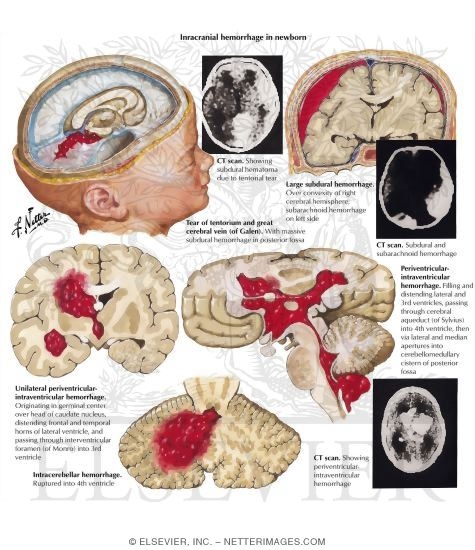

Intracranial Hemorrhage in Newborn